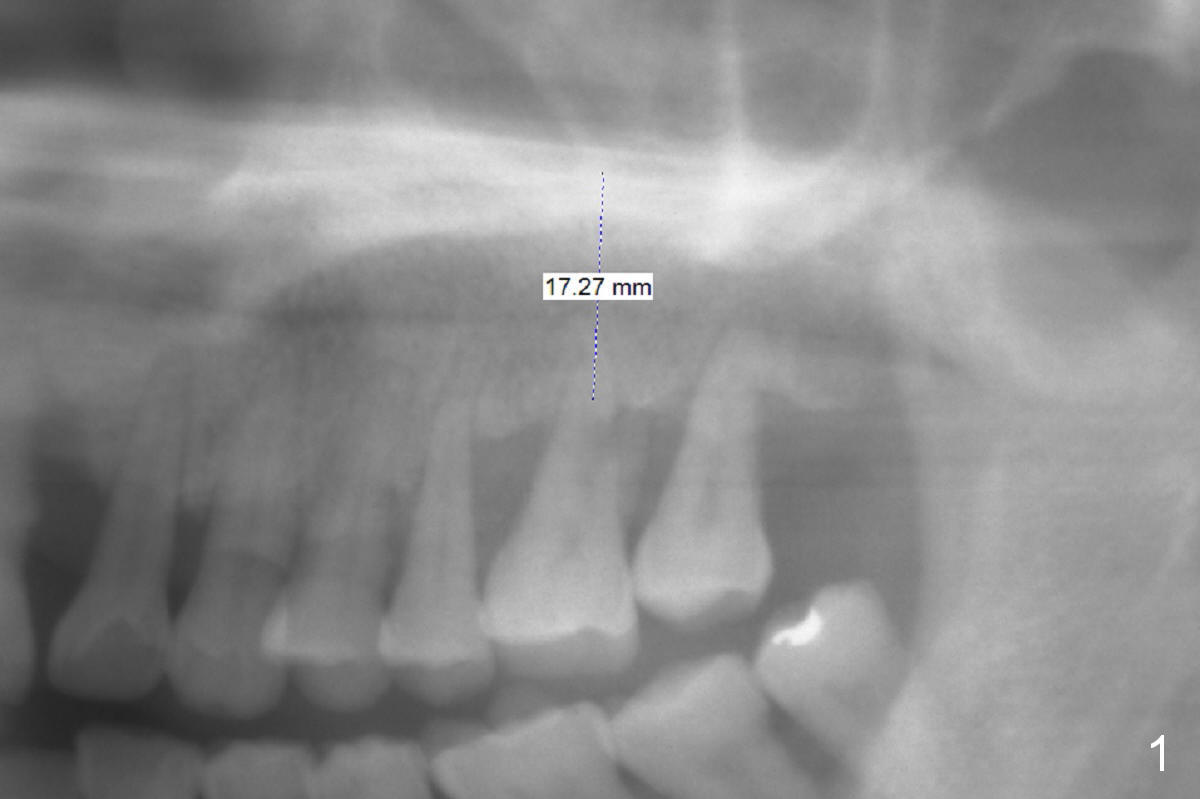

The teeth #14 and 18 of a 46-year-old man become symptomatic 1 month after #4 implant placement. While the socket at #14 is shallow, the apical bone is abundant (Fig.1). The longest IBS implant should be safe (13 mm, Fig.2). In contrast, the socket at #18 is relatively deep, the apical bone is short (Fig.3). A shorter implant (11 mm or less, Fig.4) should be chosen. Osteotomy in the new bone should be 4 mm. Try in a 5x9 mm dummy implant at #18. No antibiotic is used for socket treatment. The bone density in the mandible should be high (drills), whereas that in the maxilla may be low (expanders) or medium (drills). Preop exam will decide which tooth needs treatment first. Take photos PRN.